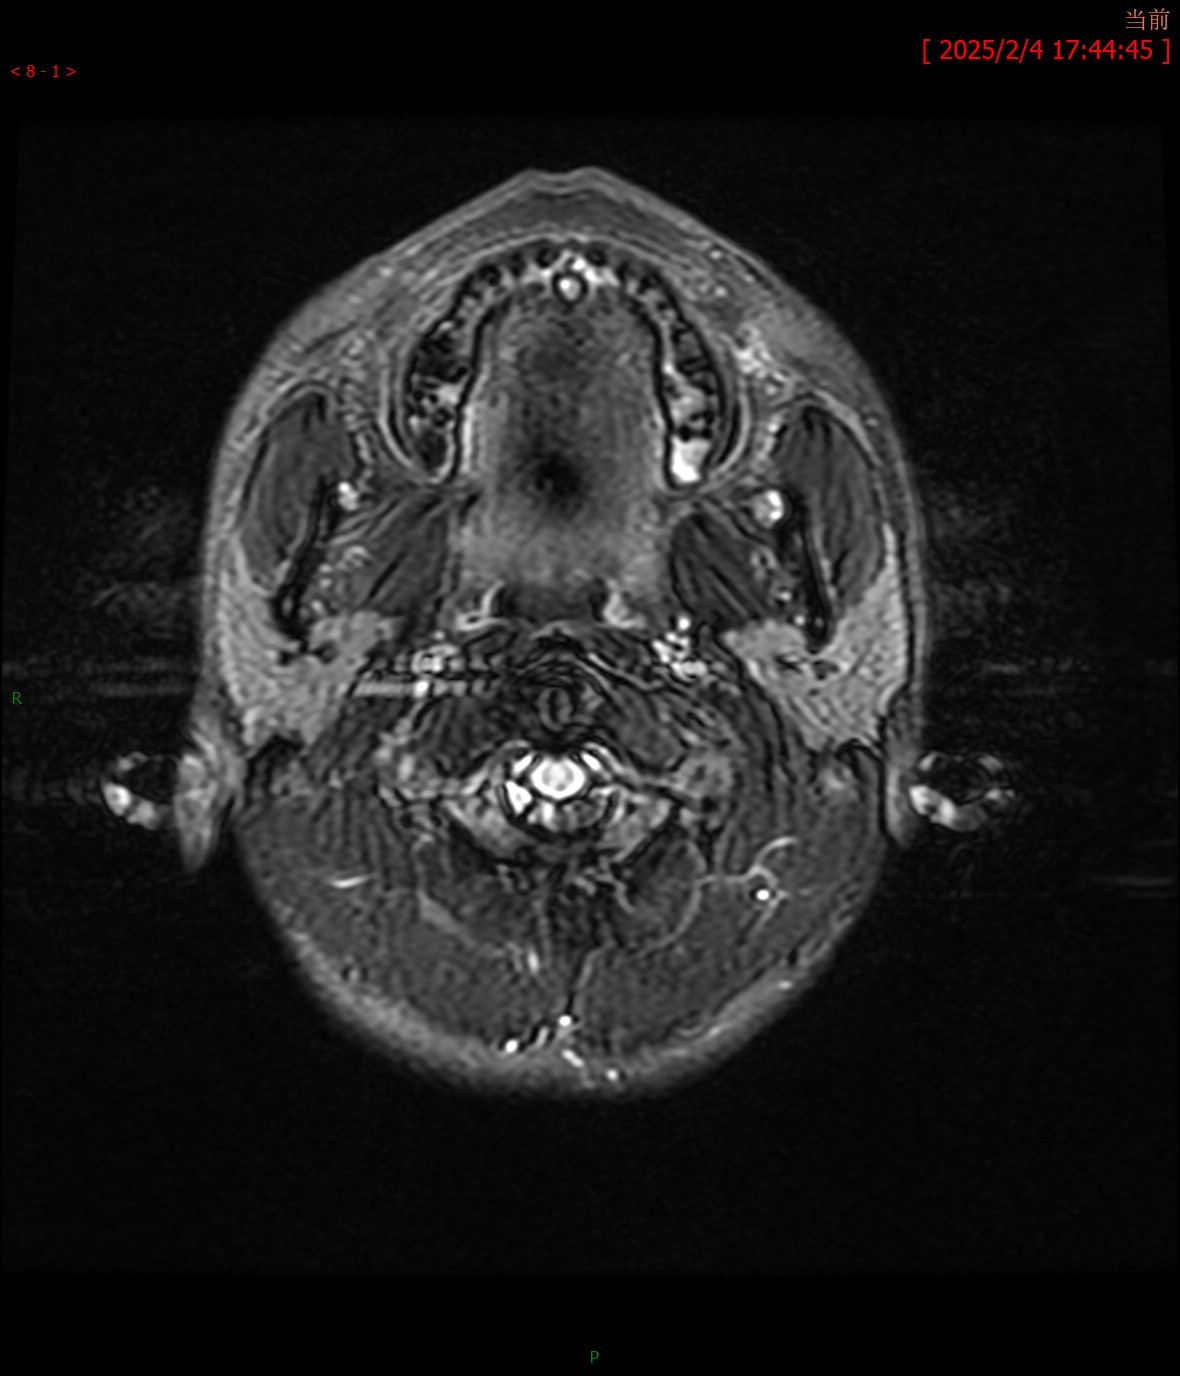

T2WI横轴位 T2FLAIR横轴位

MRA颅脑MR平扫:双侧桥臂、右侧小脑半球、延髓、桥脑、中脑、双侧豆状核、壳核可见多发斑片状稍长T1、T2信号,边界不清,病灶于T2FLAIR呈高信号,大致呈对称性分布。脑室系统轻度扩大,脑沟、脑裂增宽,中脑、小脑体积缩小,中线结构未见移位。

影像学诊断:1. 双侧桥臂、右侧小脑半球、脑干及基底核团多发异常信号伴脑萎缩改变,符合肝豆状核变性颅脑表现;2. 颅脑MRA未见明显异常。

最常见的影像表现为T2WI和T2-FLAIR图像上双侧壳核(70%)、尾状核(60%)、丘脑腹外侧(55%~60%)和中脑(50%)出现对称性高信号,这些区域反映了该病铜沉积的选择易损性特征;有时也可见脑桥(20%)、延髓(10%~15%)和小脑(10%)高信号,大脑白质(25%)和小脑白质(10%)可见局灶性或弥漫性融合状高信号。其机理主要是铜沉积于脑组织中,造成反应性水肿、神经元及胶质细胞缺失、海绵样变性和胶质增生,进而引起不可逆性的空腔和囊变。在未经治疗或治疗效果不佳时,随病程的延长,铜沉积逐渐增多,由于铜顺磁性作用,最终可形成T2WI低信号。T1WI图像上病变信号强度多样,部分病例的受累区表现为低信号,而部分病例则表现为高信号,类似慢性肝性脑病,反映了铜的顺磁性效应。对称性基底节异常信号同时伴有脑干病灶是该病的影像特征。当病变发展到一定程度时,随着神经元及胶质细胞广泛坏死、变性,常出现基底核团及脑干萎缩表现,甚至可出现全脑萎缩。